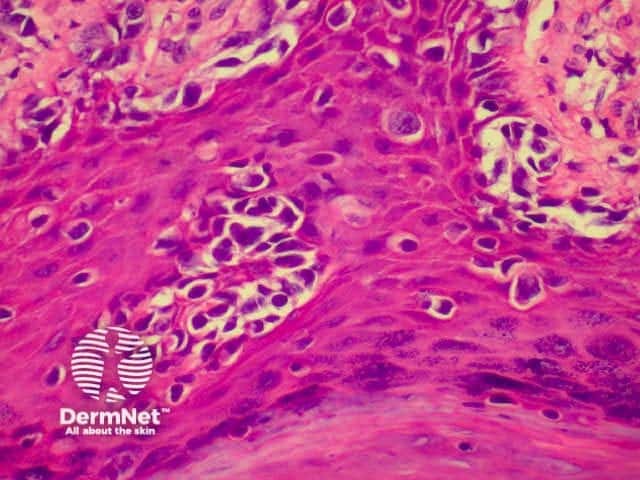

SCC is characterised by proliferation of irregular nests of abnormal squamous cells arising from the epidermis and invading the dermis. Tumours are traditionally divided into well, moderately or poorly differentiated tumours by a subjective assessment of how significantly the tumour cells differ from normal keratinocytes. In general, the greater the degree of keratinization, the better differentiated the tumour is thought to be. Except in the case of very poorly differentiated tumours, this does not have a great bearing on prognosis. More important is the depth and irregularity of invasion, particularly the presence of perineural infiltration, which is associated with a much higher rate of recurrence if not widely excised. The site of the lesion is also important; tumours of the lips and ears have a considerably higher rate of metastasis to lymph nodes.

There are several descriptive variants of SCC including spindle cell SCC and acantholytic (or adenoid or pseudoglandular SCC). These mainly are of note due to the difficulty of diagnosing the tumour as SCC, but they may also imply a slightly worse prognosis. A further rare variant is verrucous carcinoma, a lesion in which the histology has a deceptively benign appearance in that there is very little cytological abnormality. Diagnosis in these cases may be delayed and the diagnosis may not be made until several biopsies have been performed. These tumours recur locally, but do not generally metastasise.

From the above comments it can be seen that the histological features of SCCs can vary, but in general are:

Pathology of SCC Pathology of SCC Pathology of SCC Pathology of SCC